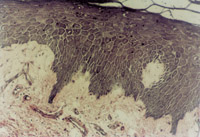

原位切取創(chuàng)面組織病理切片檢查,見壞死上皮組織間有大量顆粒樣組織,新生上皮細胞和膠原纖維組織呈團樣增生,并可見到典型的類似于胎兒皮膚結構的皮膚胚胎基(embryonic base,EB)(圖5-3-4a,5-3-4b)。MEBT治療10天后,在創(chuàng)面邊緣取上皮組織病理切片可見到較原始的上皮組織。

5-3-4a 新生上皮組織和膠原纖維增生,可見典型EB(皮膚胚胎基) HE×40

5-3-4b 新生上皮組織中可見微血管,膠原纖維和上皮細胞(干細胞)形成的皮膚胚胎基組織  HE×40